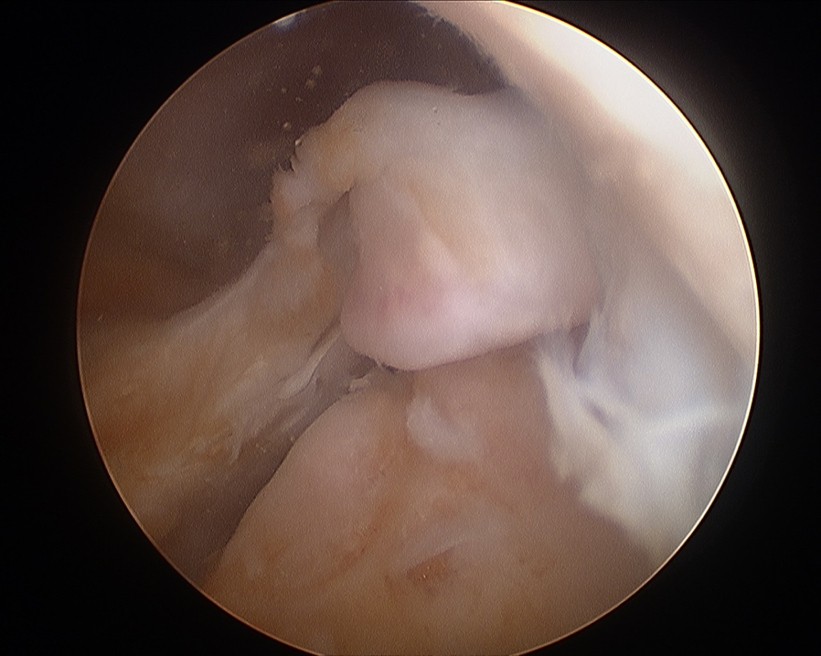

Arthroscopy

Have to look either posteromedial or posterolateral to identify